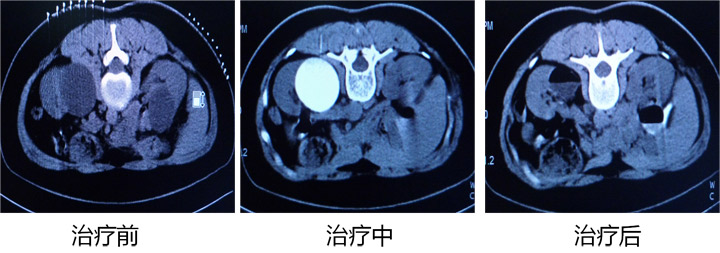

以下是成功病例的CT影像对比:

男,78岁,肝巨大囊肿,CT引导穿刺引流聚桂醇硬化术